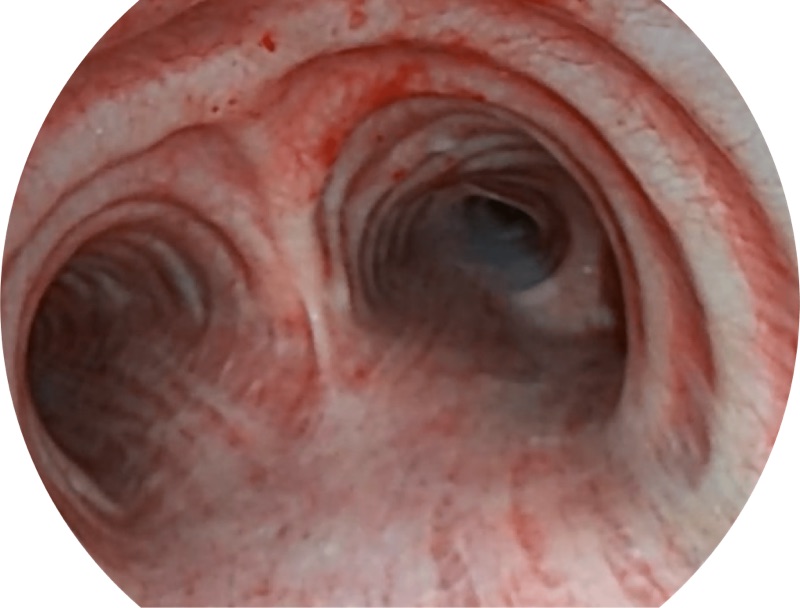

• 高清画质

帮助医生更加清晰地观察气管表面病灶

• 白光